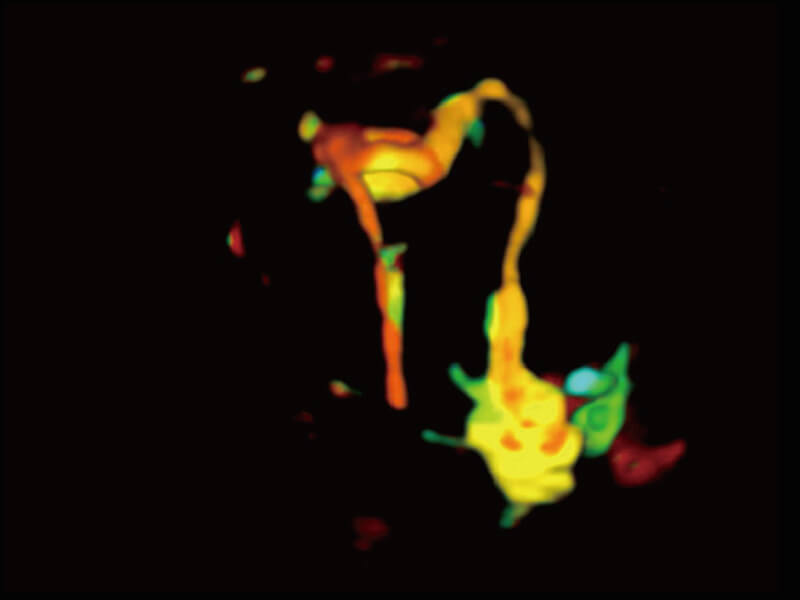

S60探头工艺,从前端信号处理每一个环节采集无损声学数据,真实还原组织原貌,再现解剖细节。

超宽频带技术,为容积成像带来优质的二维图像基础,为您呈现丰富的结构细节,栩栩如生地展示宝宝的宫内形态以及各种组织的立体结构。